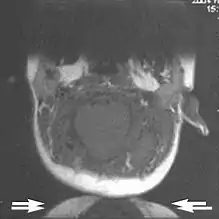

Metal artifacts

Metal artifacts occur at interfaces of tissues with different magnetic susceptibilities, which cause local magnetic fields to distort the external magnetic field. This distortion changes the precession frequency in the tissue leading to spatial mismapping of information. The degree of distortion depends on the type of metal (stainless steel having a greater distorting effect than titanium alloy), the type of interface (most striking effect at soft tissue-metal interfaces), pulse sequence and imaging parameters. Metal artifacts are caused by external ferromagnetics such as cobalt containing make-up, internal ferromagnetics such as surgical clips, spinal hardware and other orthopaedic devices, and in some cases, metallic objects swallowed by people with pica.[3] Manifestation of these artifacts is variable, including total signal loss, peripheral high signal and image distortion (Figs 3 and 4).[1]